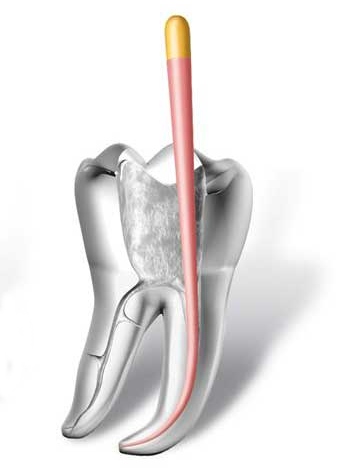

• otturazione di tutto l'endodonto mediante materiali termoplastici (guttaperca) e cementi biocompatibili